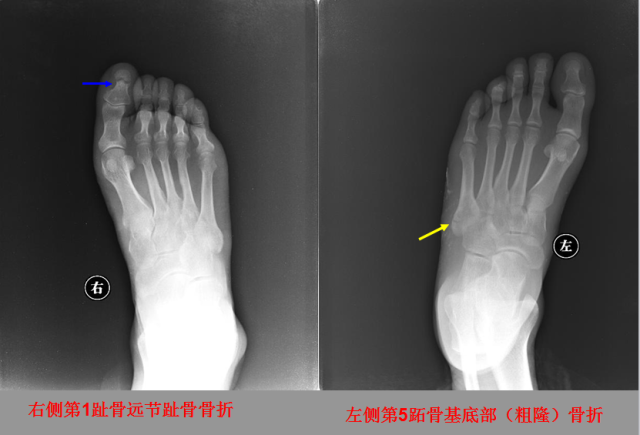

骨折篇

定义:骨折{Fracture}是指骨的完整性和连续性的折裂或粉碎。包括创伤性骨折、疲劳性骨折和病例理性骨折。 临床上以创伤性骨折*常见。